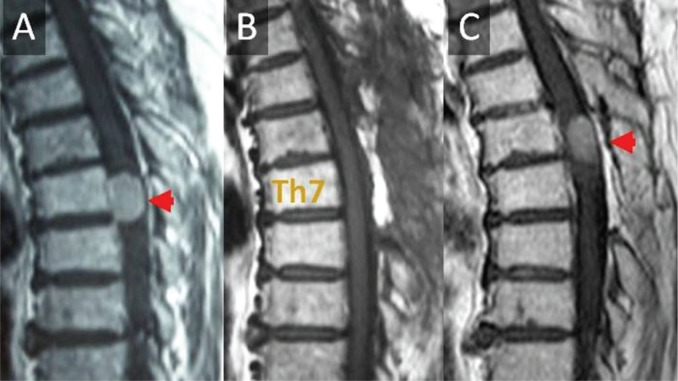

对于Simpson级切除后的两个复发病例,一个与2型神经纤维瘤病(NF2)相关。该患者在初次手术后9年复发(图1)。另一个辛普森二级切除后复发的病例在初次手术后20年复发。接受不完全切除(辛普森ⅳ级)的3名患者均无肿瘤复发。

图1。患者为一名76岁女性,其Th7级脑膜瘤经辛普森ⅱ级切除术治疗,病理诊断为砂粒脑膜瘤。她在初次手术后9年肿瘤复发。核磁共振显示(A)术前,(B)术后即刻,(C)初次手术后9年。